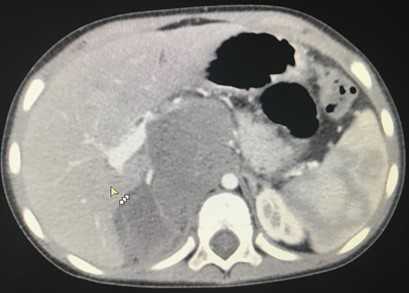

Компьютерная томография брюшной полости и забрюшинного пространства

Компьютерная томография более детально дает информацию об анатомическом отношении опухоли к окружающим тканям и органам, позволяет оценить структуру опухоли (рис. 5).

Рис. 5. КТ нейрогенного образования забрюшинного пространства справа